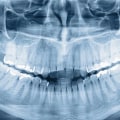

Dental X-rays are an essential tool for detecting early signs of oral health problems. These machines use radiation to produce radiographic images of the teeth, gums, and jawbone. The resulting images can reveal dental issues that may not be visible during a routine checkup.

In recent years, digital technology has revolutionized the way we take dental X-rays. Digital X-ray machines emit less radiation than traditional film-based systems and produce higher-quality images in less time. This means patients are exposed to less radiation while receiving more accurate diagnoses. When taking dental X-rays, it is important that the dentist or hygienist takes necessary precautions to minimize exposure to radiation. Patients should also inform their healthcare provider if they are pregnant or suspect they may be pregnant as this will affect whether or not dental X-rays can be taken safely.

By using modern X-ray machines and digital technology, dentists can detect potential oral health problems before they become serious issues. Regularly scheduled appointments for dental exams with X-rays can help catch cavities before they advance and spot other issues like gum disease or abscesses which require treatment from your dentist right away.